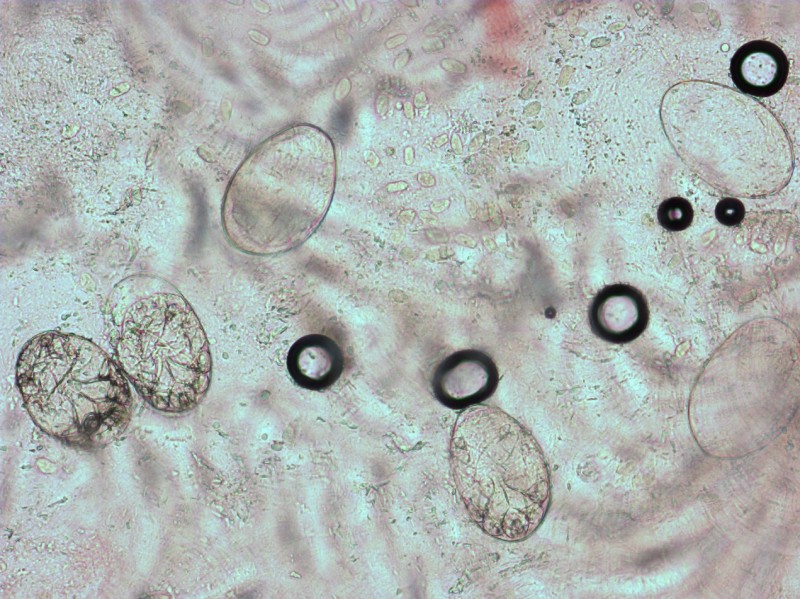

Schurftmijt met ei in onderlichaam en een hele sliert eieren er achteraan. |

Diagnostiek:Preparaat maken: zoek een

papeltje of gangetje op tussen de vingers of op een andere voorkeurslokalisatie.

Snij met een mesje de bovenste laag van de huid af. De mijt leeft in de hoornlaag,

maar om een goed en groot genoeg preparaat te krijgen is het beter om iets van

de epidermis mee te nemen. Breng het in KOH onder een dekglaasje. Zoeken naar

mijten, gangetjes en eieren. Een andere methode is de dermatoscopie, waarbij

| 2 jonge

mijten nog in het ei |

serie

eieren, sommige leeg |